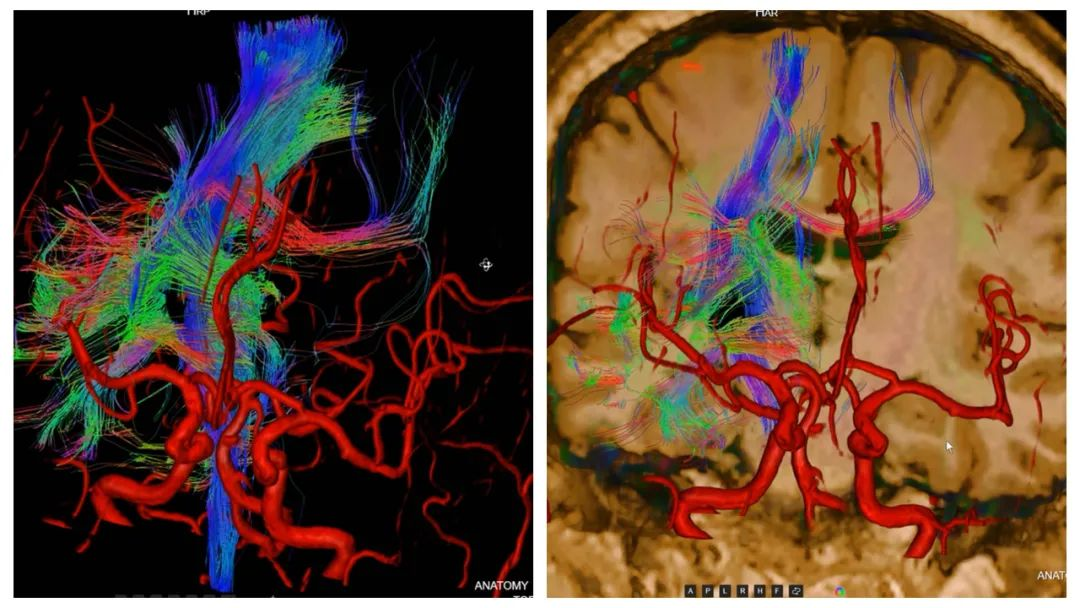

联合神经功能成像

左:头颈部TofMRA 右:全脊柱MR

近日,我院放射科新引进了3.0T高端磁共振扫描仪,其功能更为强大,借助新设备,我院目前已常规开展颅脑SWI、fMRI、PWI、ASL、DTI、MRS、IVIM等神经高级功能成像,以及头、颈部血管壁MR高分辨成像、全脊柱MR、乳腺MR,心脏MR等高端检查,为患者提供更多、更精准的扫描与诊断服务,为临床诊治提供更多帮助。